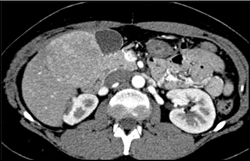

Diagnosis

Hepatoma